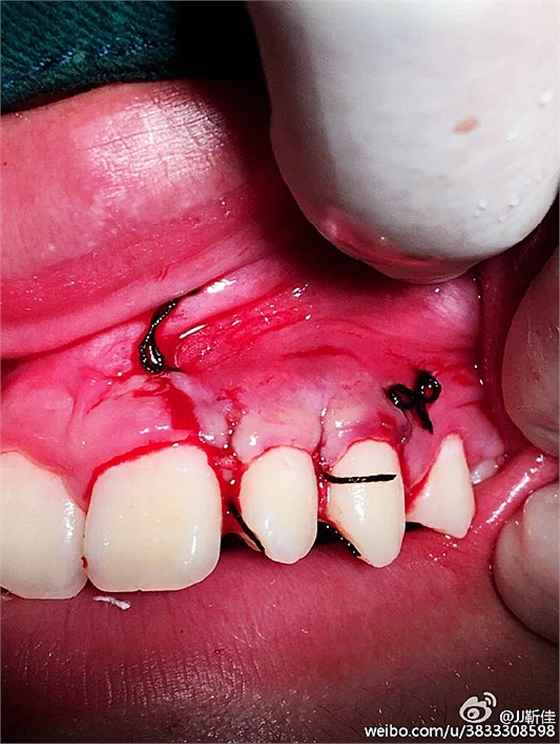

局部麻醉。

額外牙拔除

好大的額外牙

植入骨膏

覆蓋骨膜

縫合